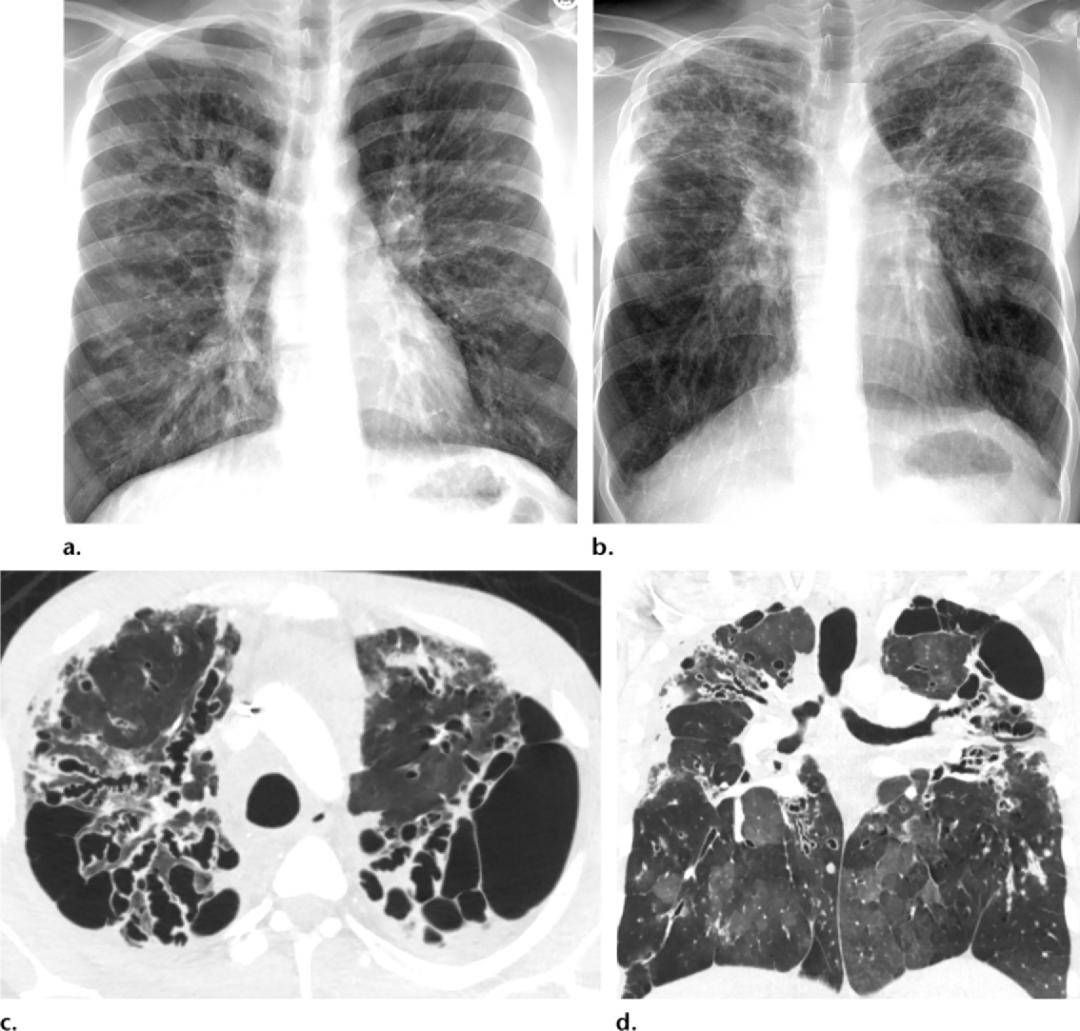

ct显示肺部支气管扩张伴感染

图片尺寸1324x1080